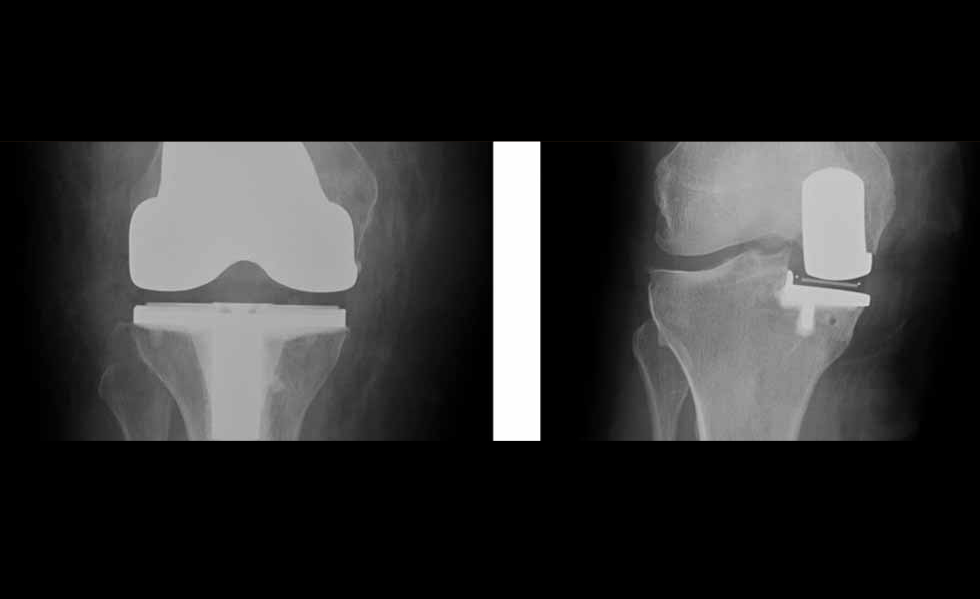

Our services are lead by Simon Palmer who is a Consultant Orthopaedic Surgeon with specialist training and experience in all aspects of knee surgery, including minimally invasive surgery and partial knee replacement.